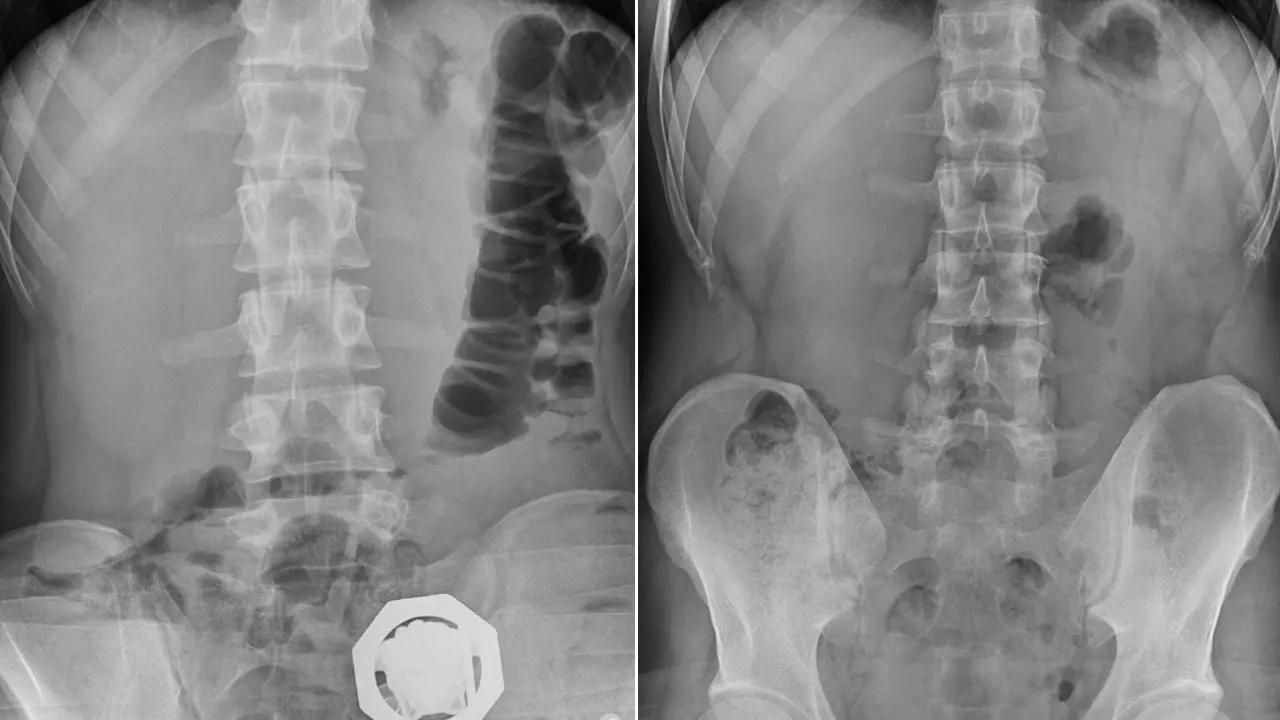

Tedirgin haller sergilemeleri ve rahatsızlık belirtisi vermeleri üzerine, 4 şüphelinin çekilen röntgenlerinde midelerinde 121 parça halinde 840 gram eroin tespit edildi.

DHA- Diyarbakır'da, bir otomobildeki 4 şüphelinin midelerinde 121 parça halinde 840 gram eroin tespit edildi. Uyuşturucu çıkarılırken, 4 şüpheli tutuklandı.

İl Emniyet Müdürlüğü Narkotik Suçlarla Mücadele Şube Müdürlüğü ekiplerince yapılan çalışmalarda, doğu illerinden Diyarbakır'a geldiği tespit edilen otomobil, Bağcılar Mahallesi'nde durduruldu. İçinde bulunan 4 şüphelinin üst aramalarında herhangi bir suç unsuruna rastlanılmadı.

Ancak şüpheliler, tedirgin haller sergilemeleri ve rahatsızlık belirtisi vermeleri üzerine, hastaneye götürüldü. 4 şüphelinin çekilen röntgenlerinde midelerinde 121 parça halinde 840 gram eroin tespit edildi. Uyuşturucular, yapılan tedavinin ardından çıkarıldı. Şüpheliler, işlemlerinin ardından sevk edildikleri adliyede çıkarıldıkları mahkemece "Uyuşturucu veya uyarıcı madde ticareti yapma veya sağlama" suçlarından tutuklanarak cezaevine gönderildi.